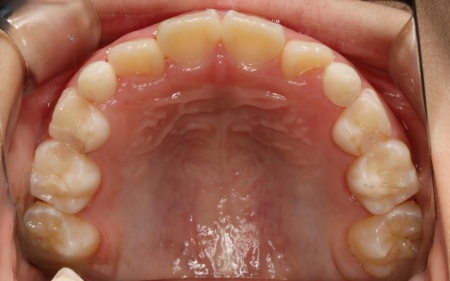

治療後

治療中は、スクリューを少しずつ回すことで顎の骨が徐々に横方向に拡大されていき、永久歯が生えるためのスペースを十分に確保することができました。

拡大治療が完了したあとは、顎の状態を安定させるためのリテーナー(保定装置)を装着し、治療を終了しています。